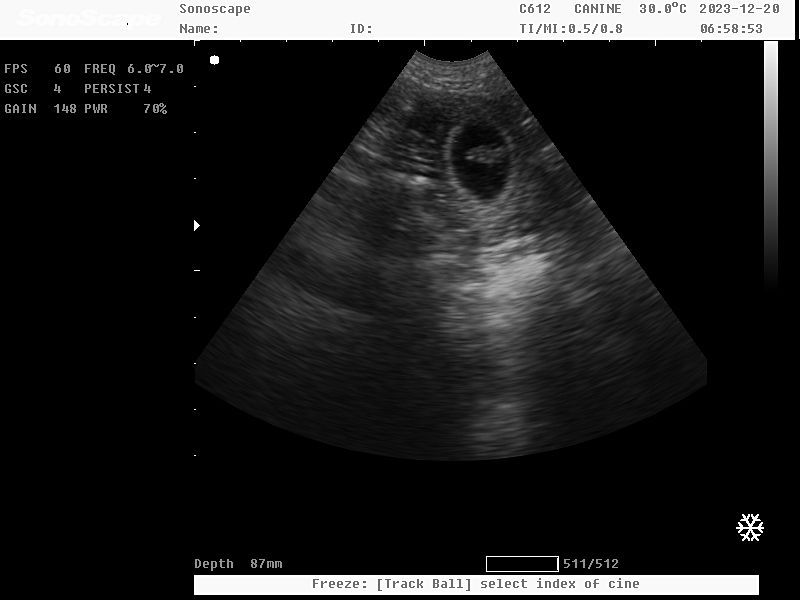

Wir waren beim Ultraschall <3

Der Valentinstag hat seine positiven Vibes spielen lassen ;-))

Wir freuen uns auf kleine Osterhasen -

unseren Corgi M-Wurf :-))))